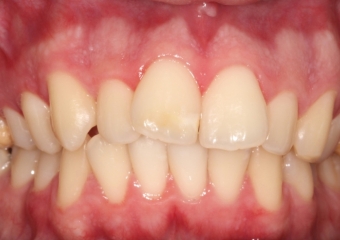

Mordida inicial - Clínica Cliniface

Mordida inicial